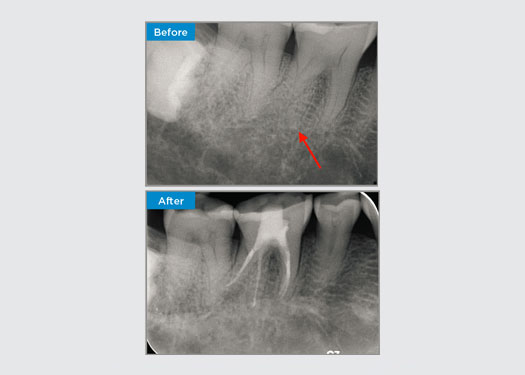

Le patient s’est présenté avec une parodontite apicale asymptomatique sur la dent 34. Sur la radiographie préopératoire, la dent 34 présentait deux racines visibles. Cependant, un balayage CBCT a confirmé qu’il s’agissait d’une prémolaire à trois racines et que les canaux se divisaient en trois au milieu de la racine. Une sélection minutieuse des limes est essentielle pour cette dent délicate.

Dr Jack Lin, Endodontiste, Sydney, NSW Australie

Dans cette situation, la préservation de la structure de la dent/racine est essentielle pour réduire le risque de déviation, de déplacement, de fermeture, de perforation et de fracture de la racine. La sélection des cas, le diagnostic et la planification du traitement préalable sont importants. Le choix de la lime endodontique en fonction de sa flexibilité, de son efficacité et du respect de l’anatomie naturelle de la racine est essentiel.